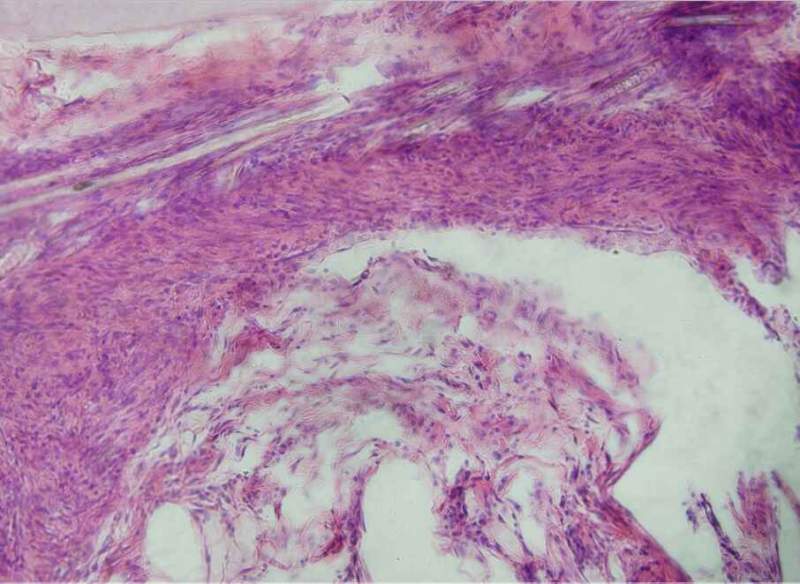

Çë°ïæ¿´ÏÂÕâÇÐÆ¬ÄÜ˵Ã÷ʲôÂ𣿺ÚÉ«µÄÊÇÎÒÇÐÆ¬¼¼ÊõÎÊÌâÂ𣿠ÒÑÓÐ2È˲ÎÓë

ÕâÈýÕÅÊDz»Ò»ÑùµÄ£¬Ò»¸öÊÇ´ÆÊóÓвÄÁÏ£¬ÁíÍâÁ½¸ö·Ö±ðÊÇ´ÆÐ۵Ŀհס£ ·¢×ÔСľ³æAndroid¿Í»§¶Ë |

Â¥Ö÷£¬ÄãµÄÇÐÆ¬ÖÊÁ¿È·Êµ²»Ì«ºÃ£¬Ê×ÏÈÇÐÆ¬Ê±Óе¶ºÛ£¬ÔÙ¾ÍÊÇÇÐÆ¬Ì«ºñ£¬ÇÐÆ¬²»ÔÚÍ¬Ò»Æ½Ãæ£¬×Ðϸ¿´µÚ¶þÕž۽¹²»ÔÚÍ¬Ò»Æ½Ãæ£¬È¾É«Ê±Ã»ÓÐÏ´¸É¾»£¬ÓÐÔÓÖÊ£¬ÄÇЩºÚÉ«µÄÓ¦¸ÃÊÇÔÓÖÊ£¬Ò²ÓеãÏñȾɫ²½Öè²»¹æ·¶Ôì³ÉµÄ ·¢×ÔСľ³æIOS¿Í»§¶Ë |

ÇÐÆ¬ºñ¶È0.8ÎÒ²»¶®£¬Ò»°ãÇÐÆ¬ºñ¶ÈΪ4?6΢Ã×£¬Íê³É²»ÔÚÒ»¸öÆ½ÃæµÄÔÒòÒ»ÊÇÆ¬×ÓÌ«ºñ£¬¶þÊÇÇÐÆ¬Ã»Çкã¬ÖÁÓÚȾɫ³ÊºÚÉ«ÄÇÓÖ¿ÉÄÜÊÇÄǸöѪ¹ÜµÄÄÚÆ¤Ï¸°ûÓÐÒìÊÈÐÔ£¬²»ÓùÜËû£¬Ò²ÐíÏÂÒ»ÕÅÇÐÆ¬¾ÍûÁË ·¢×ÔСľ³æIOS¿Í»§¶Ë |

ÕâÑù°¡£¬ÇÐÆ¬ºñ¶ÈÊÇ0.8µÄ£¬ÇÐÆ¬²»ÔÚÒ»¸öÆ½Ãæ¾Í²»¶®ÁË¡£¾Û½¹µÄ»°£¬Õâ¸öÊDZðÈ˸øÅĵģ¬ËýÃÇÄǾ³£ÅÄ£¬Ó¦¸ÃÊÇÂù¶®µÄ°¡¡£È¾É«Êǰ´ÕÕ²½ÖèÀ´µÄ£¬²»¹ýËÕľ¾«È¾É«ºó£¬ÎÒ¾õµÃÓ¦¸ÃÓô¿Ë®Ï´£¬µ«ÊǶԷ½ÈÃÎÒÓõÄ×ÔÀ´Ë®¡£Õâ¸ö²»ÖªµÀÓÐûÓÐÓ°Ïì¡£µ«ÊÇËùÓеͼÊÇÕâôϴµÄ°¡£¬²»ÄÜÖ»ÓÐÕâ¸öÓÐÎÊÌâ°É¡£¡£